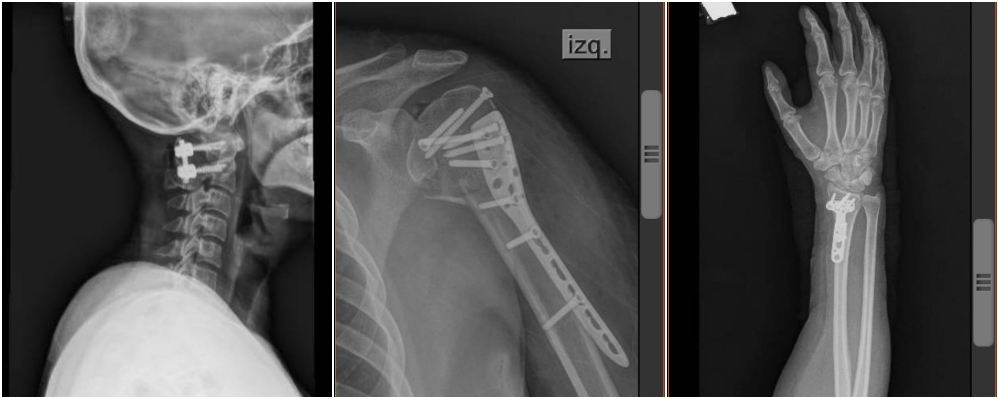

Al arribar al sanatorio privado, Paez contó que “en la guardia se agarraban la cabeza porque yo estaba toda lastimada, la boca cortada, la cara ensangrentada, porque mi hermana me limpió pero no salían”. Y contó que en las radiografías y tomografías “vieron que tenía fractura 1 y 2 de cervical, los dos hombros, una muñeca, una costilla y el omóplato fracturados y eso no lo vieron (en el Madariaga), no revisaron mis placas. En el Boratti bajaron corriendo las enfermeras, los médicos, el médico especialista en cervical, el neurocirgujano, me pusieron el collar ortopédico y decían no la toquen”.

Contó que a raíz de la mala situación, quedó internada desde el 3 de agosto hasta hace tres días en el sanatorio cuando le dieron el alta, sin antes realizarle varias cirugías. “Volví a caminar, porque estuve postrada en la cama desde el 3 al 11 de agosto cuando fue la primera cirguía de cervical. Y todo esto lo viví porque no revisaron una placa o no lo vieron”.